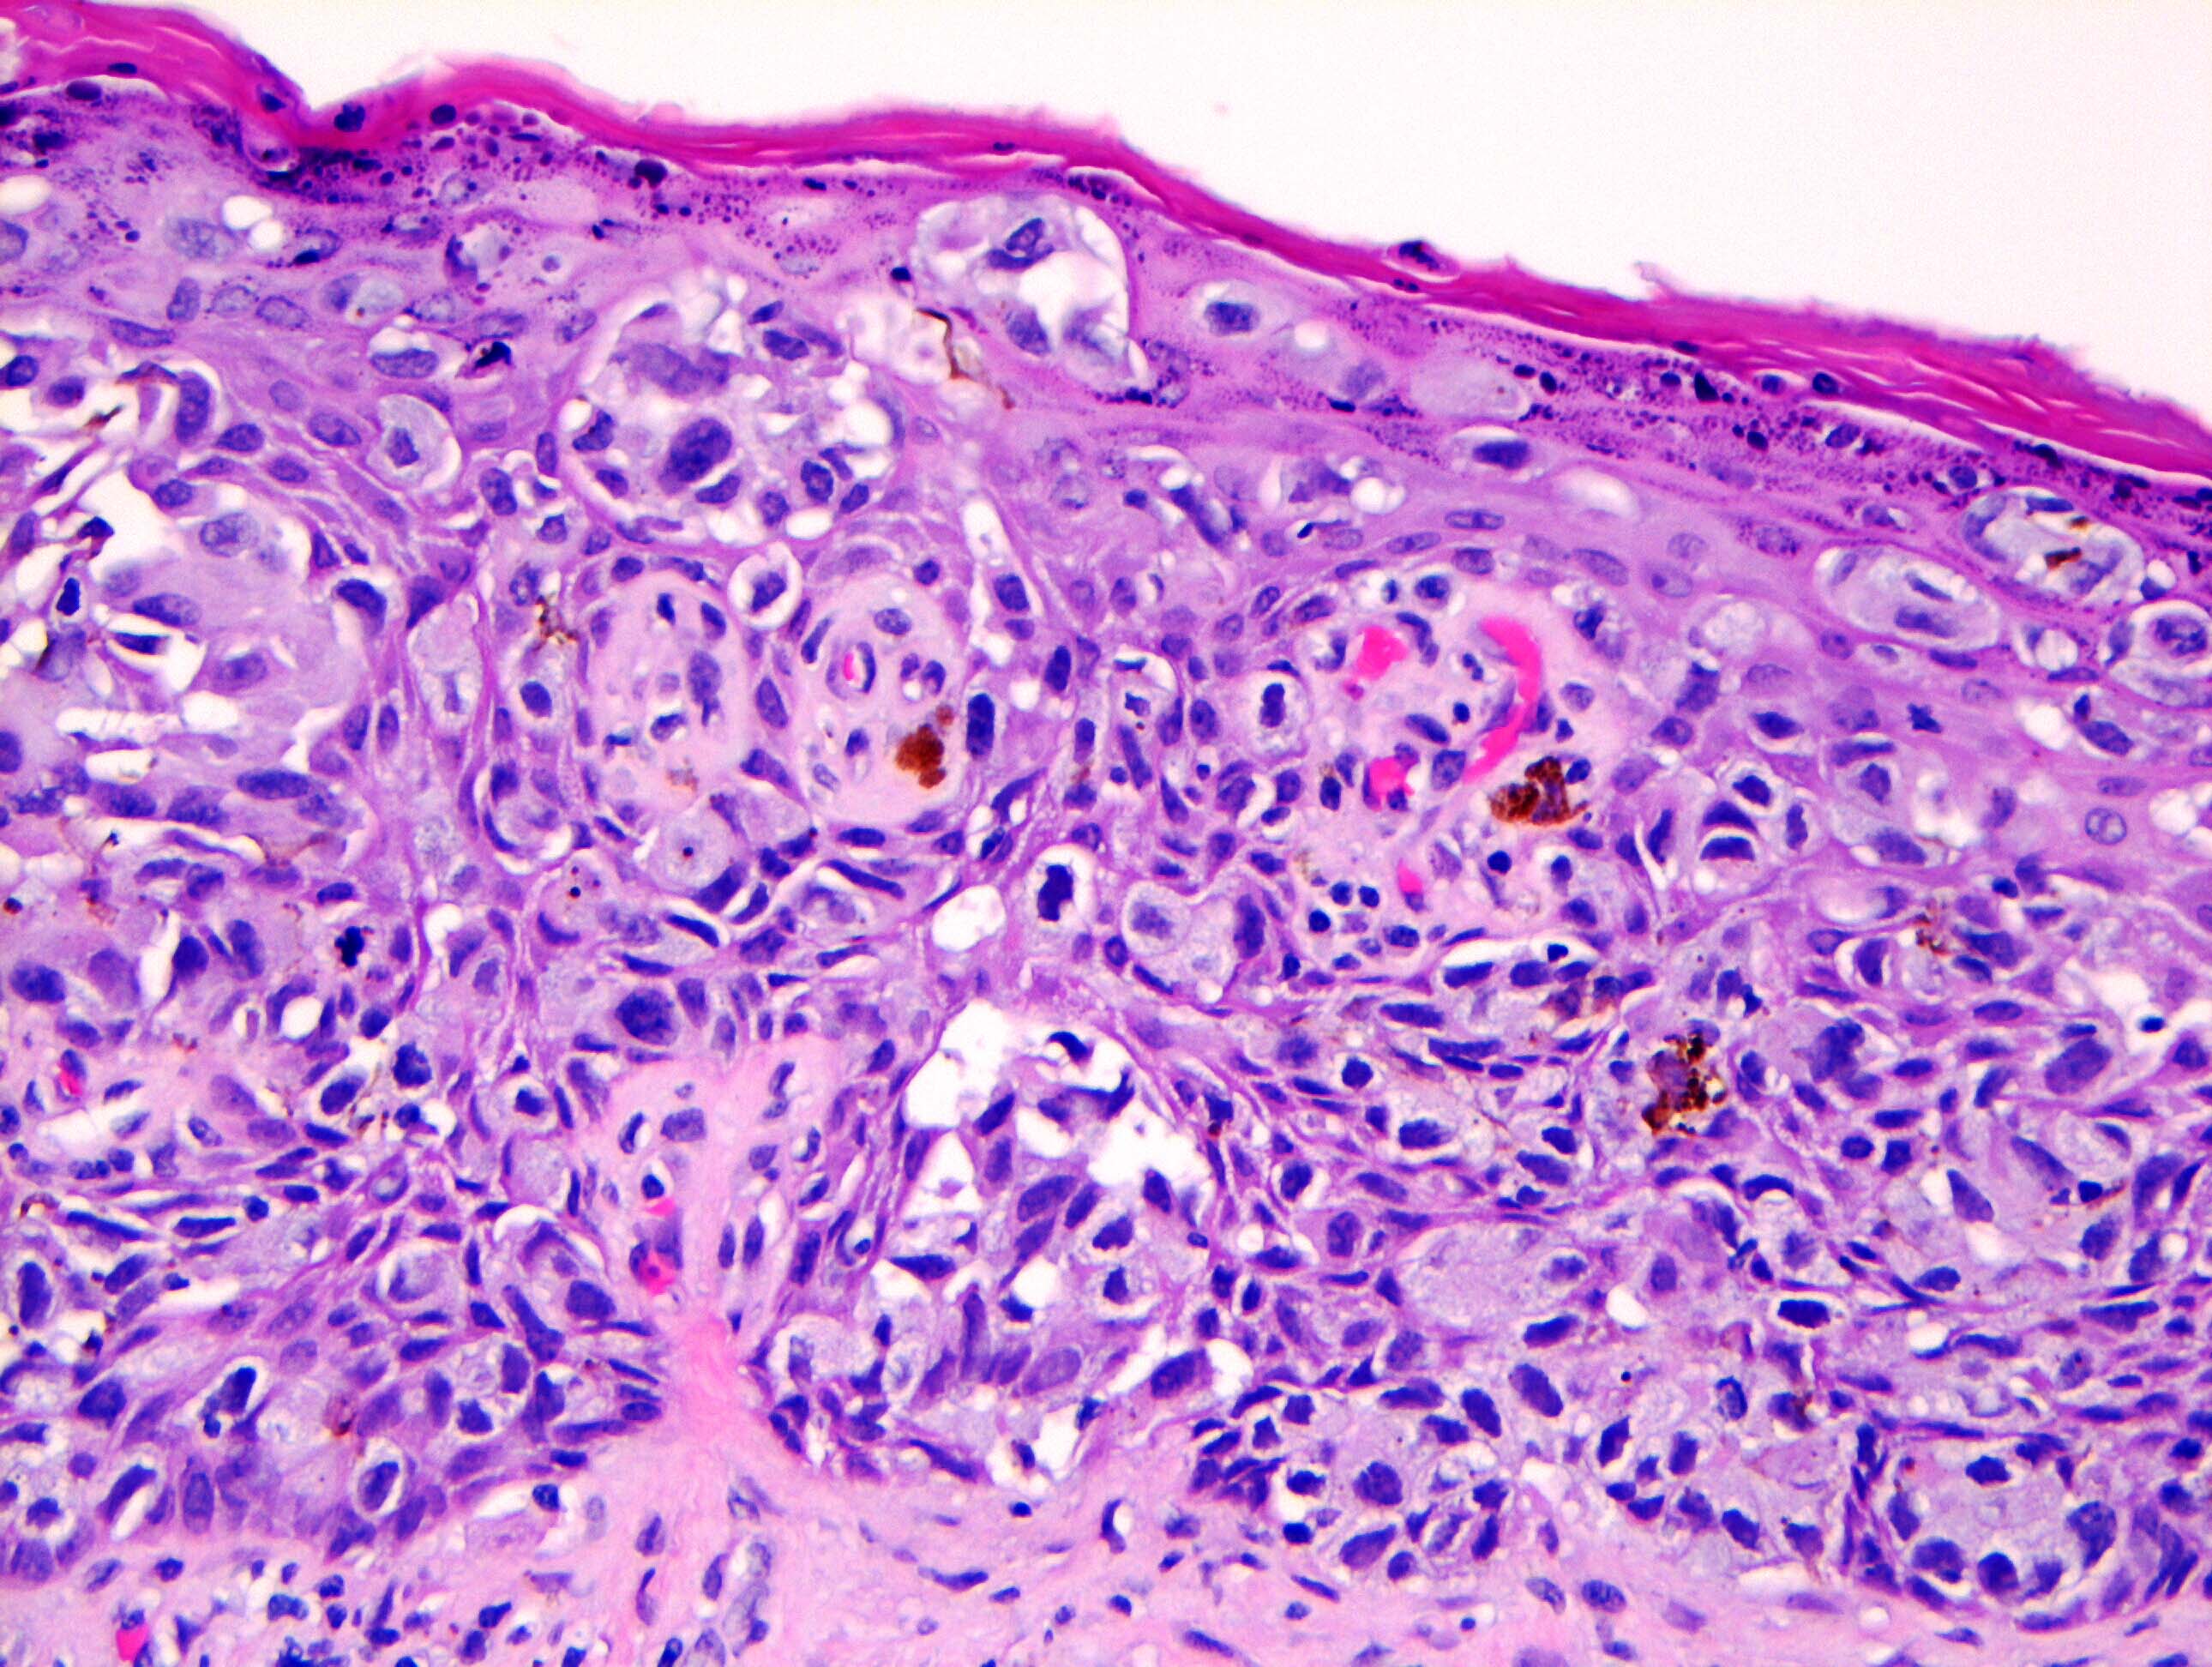

- Single cells or clusters of cells spread throughout the epidermis

- Cells have abundant pale cytoplasm, large irregular nuclei with prominent nucleoli

- Underlying dermis may have chronic inflammation

- Epidermis with hyperkeratosis and possibly ulceration

- Florid cases can show gland formation

- Paget cells may phagocytose melanin, mimicking melanocytes

Microscopic (histologic) images

Contributed by Anna Biernacka, M.D., Ph.D. and Mary Ann Gimenez Sanders, M.D, Ph.D.